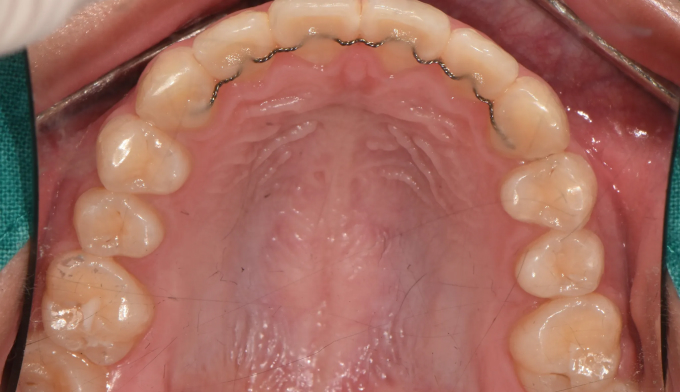

Before